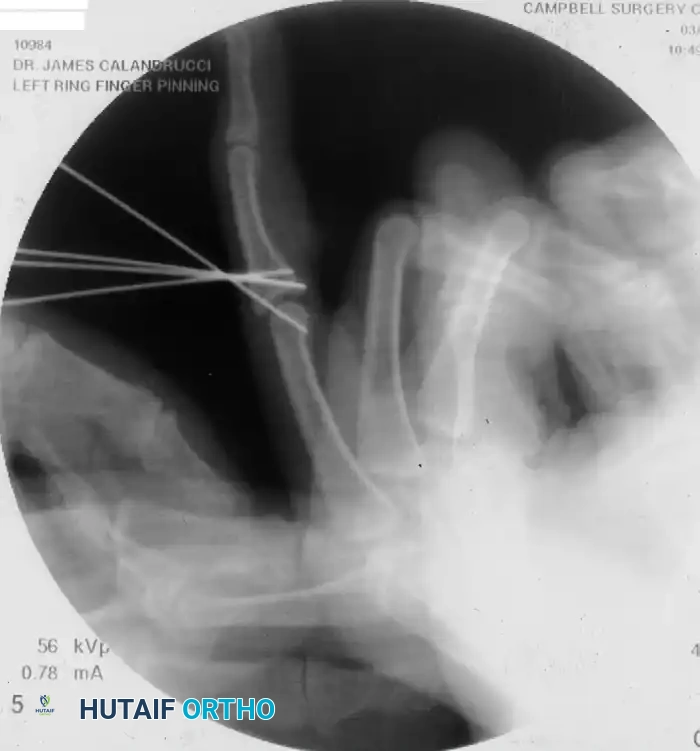

Figure 67-52 (A-C): Anterior, lateral, and oblique radiographic views of a markedly comminuted and unstable PIP joint fracture-dislocation in a 15-year-old softball player. Note the severe dorsal subluxation and loss of articular congruity.

- Primary Fixation: Fix the fragment in position using a small Kirschner wire (typically 0.028-inch or 0.035-inch).

- Trajectory: Insert the K-wire in a dorsal direction (from volar-distal to dorsal-proximal).

- Subchondral Burial: Draw the wire dorsally until its volar end lies just beneath the articular surface of the fragment. It is imperative that the wire does not protrude into the joint space, as this would mechanically interfere with joint flexion and cause rapid chondrolysis.

- Wire Trimming: Cut the wire flush with the dorsal surface of the middle phalanx to prevent soft tissue irritation beneath the extensor mechanism.

- Transarticular Pinning: Fix the joint in this position with a second, obliquely inserted K-wire crossing the PIP joint. This neutralizes shear forces across the newly fixed fracture during the early healing phase.